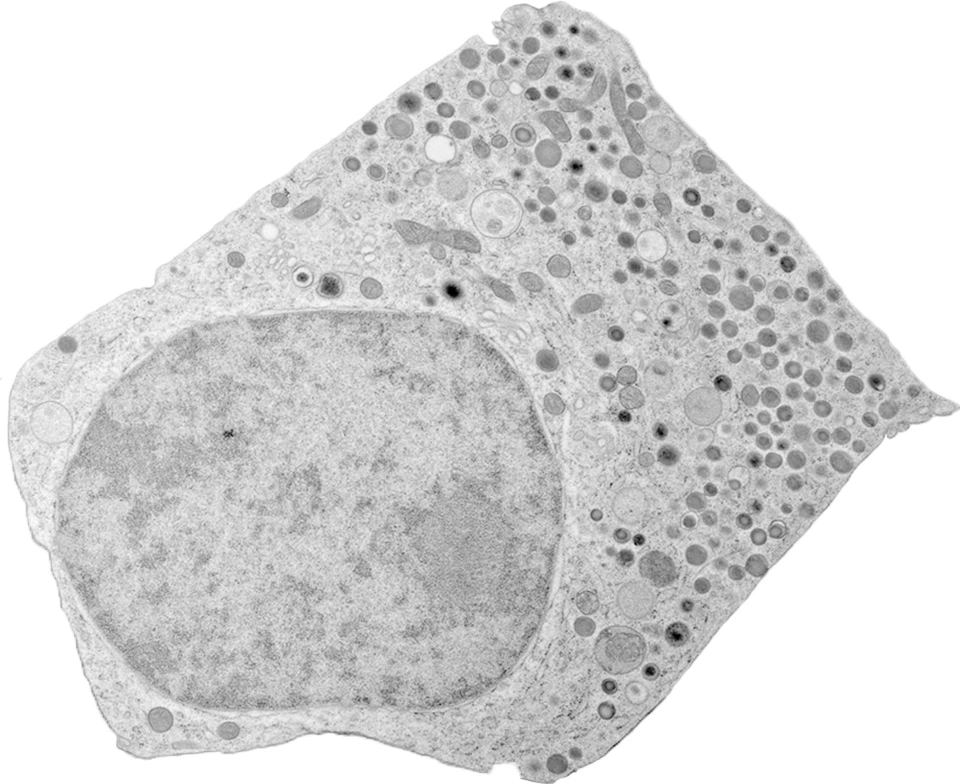

Our laboratory is interested in the cell biology of beta cells of the endocrine pancreas. Pancreatic beta cells play a key role in glucose homeostasis by releasing the glucose-lowering hormone insulin. Autoimmune destruction of beta cells leads to the development of type 1 diabetes mellitus, whereas an impairment of insulin secretion is implicated in the pathogenesis of type 2 diabetes mellitus. Our research is focused on the insulin secretory granules, i.e. the organelles devoted to the storage and regulated release of insulin in response to glucose and other stimuli.

3D FIB-SEM reconstruction of microtubule-organelle interaction in whole primary mouse β cells